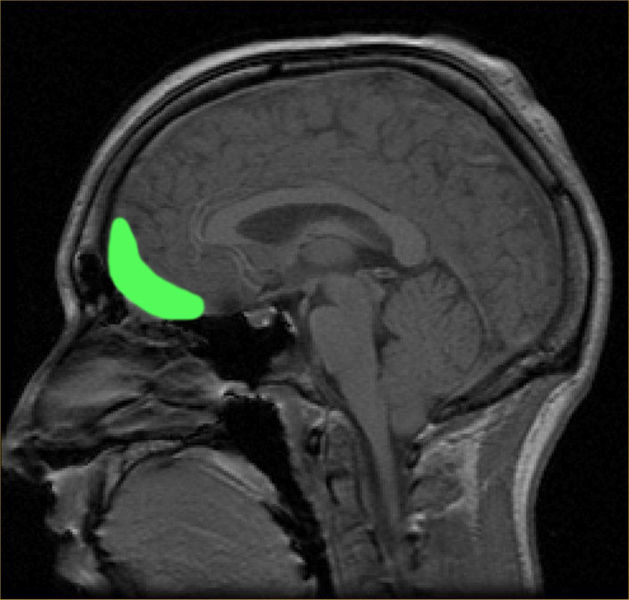

The experience was a lot of fun (thanks for having me Karen, Megan, and Sam) and introduced me to a whole body of writing on neuroscience, visual culture, and experience that I hadn’t come across at the Graduate Center. Neuroscientist António Damásio (the director of the Brain and Creativity Institute at USC) and David Freedberg (Pierre Matisse Professor of Art History at Columbia) gave keynote addresses on the agency of art and their action on our neural pathways. Looking at an artwork causes our neurons to fire, triggering a physical, non-cognitive (or at least pre-cognitive) “mirror response,” what they termed an embodied reaction to artworks. Even if we don’t raise our hands in silent pledge when we see the Horatii raise theirs in Davids’s Oath, recent neuroscience experiments tell us that neurons fire in the region of the brain responsible for contracting the muscles in our arm and lifting our limb.

Damasio and Freedberg termed this magical thinking the “as if” response – we respond to the artwork, even if only in our minds and not bodily, as if we were there undertaking the action. This implied collapsing of the distance between the artwork and our body is nothing new in light of artistic practice from the 1960s onwards (or even the andachtsbilder of the Northern Gothic) but using the conceptual framework of neuroaesthetics to tease it apart, to highlight what we intuitively understand as people invested in the arts (my brain does fire neurons when I see a work that moves me) was fascinating. It made me think of the artist-educators of the early 70s that I’ve been researching, and the ways in which they encouraged participants in their programs to abandon the primacy of cognitive responses (letting go of the immediate need for history, context, a wall label) to revel in shape, feeling, identification, embodiment in front of an artwork. Educator Philip Yenawine’s “zero-information” strategy at the Met Museum infuriated curators at the time (his methods had children moving around on the gallery floor “embodying” color and shape) yet finds new legitimacy in light of the marriage between neuroscience and art.